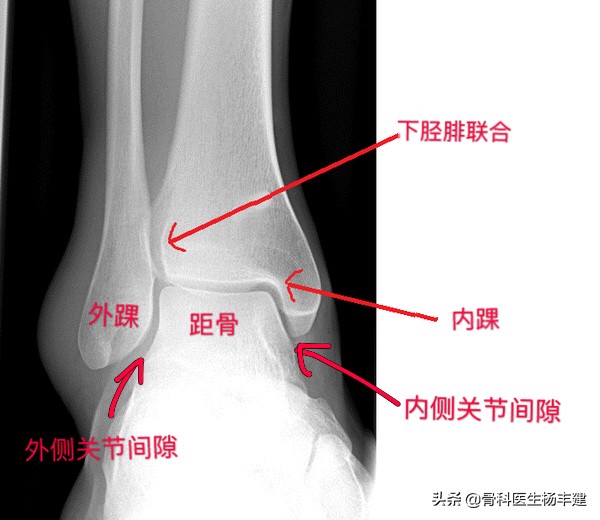

1,为了能够帮助大家理解,需要先解释一下踝关节的解剖。由于我们主要是谈骨折,所以用踝关节正位X光图像作为“模特”。

如图所示,胫骨下端、腓骨下端与距骨一起组成踝关节,其中胫骨下端构成踝关节的顶部和内踝;腓骨下端称为外踝;内踝、外踝以及顶部一起组成一个门形的结构包绕距骨,距骨所在的门形结构称为“踝穴”,距骨两侧的间隙分别称为内侧和外侧关节间隙,通常情况下内侧和外侧的间隙是均匀相等的。

踝关节正位X光图像,可以看到主要的解剖结构